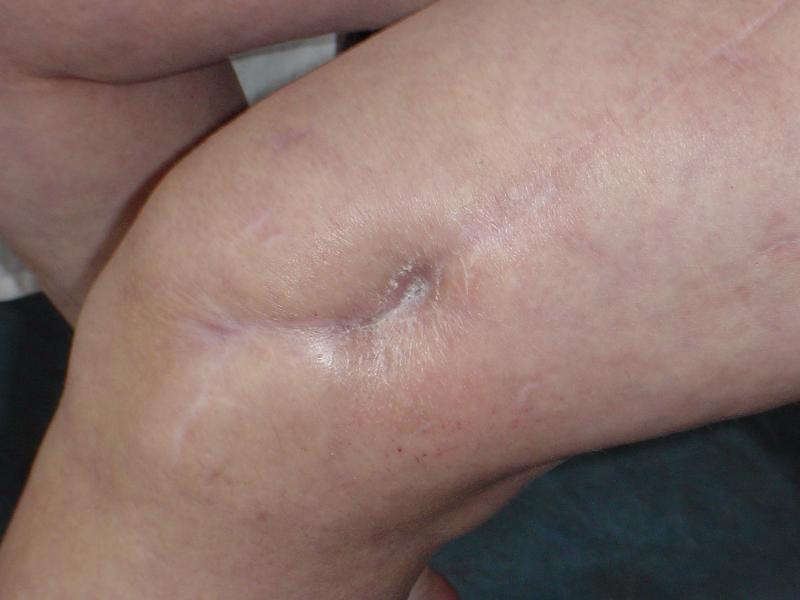

Потекло через месяц - открылось 2 свища по старому рубцу от давно удаленной пластины. На фоне гноя раза три завинчивал обратно винты, которые вылезали латерально, прямо через свищ. Потом таки провел дополнительно винты мимо гвоздя, и убрал вверху статический винт. Острый гнойный процесс стих, свищи мыла она дома дважды в день водным хлоргексидином, ходила с возрастающей нагрузкой, а к 10 мес. и свищи закрылись, и срослось. Итоговые снимки от 18 апреля 2003 г. прилагаю.